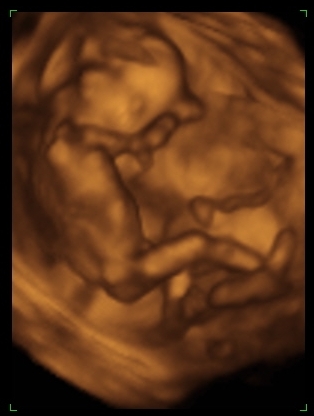

Párom meg kb ennyit hízott..... és közben a pocakom meg a derekam nő és nő. Nem értem.

De amint lesz kis időm én is készítek pocakfotót, mert már eléggé látszik.